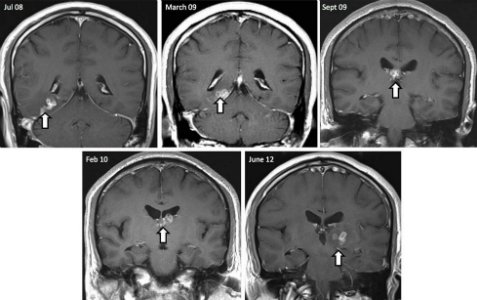

Βρετανοί επιστήμονες ανακάλυψαν ένα σπάνιο σκουλήκι – ταινία στον εγκέφαλο ενός 50χρονου Κινέζου. Πρόκειται για σκουλήκι που ως παράσιτο συνήθως μολύνει σκύλους, γάτες και άλλα ζώα. Οι γιατροί διαπίστωσαν ότι το σκουλήκι – ταινία είχε μήκος ένα εκατοστό, ζούσε τουλάχιστον επί τέσσερα χρόνια μέσα στο κεφάλι του άνδρα και του προκαλούσε τρομερούς πονοκεφάλους, επιληπτικές κρίσεις, αλλοίωση της αίσθησης της όσφρησης, ξαφνικές αναλαμπές μνήμης και άλλα νευρολογικά συμπτώματα.

Να σημειωθεί ότι οι γιατροί στο βρετανικό νοσοκομείο προσπαθούσαν επί χρόνια να καταλάβουν τι προκαλούσε τα συμπτώματα στον άνδρα, αλλά παρ’ όλη την πληθώρα των εξετάσεων είχαν αποτύχει να βρουν την αιτία, ώσπου αναγκάστηκαν να καταφύγουν σε εγχείρηση. Εκεί, βρήκαν το σκουλήκι «θρονιασμένο» σε σχήμα κορδέλας στη δεξιά πλευρά του εγκεφάλου. Οι γιατροί φοβούνταν ότι ο ασθενής έπασχε από καρκίνο.To πώς ο συγκεκριμένος άτυχος άνδρας μολύνθηκε με το σκουλήκι, παραμένει άγνωστο. Οι ειδικοί εκτιμούν ότι πιθανώς συνέβη όταν έφαγε μολυσμένο κρέας ή ήπιε μολυσμένο νερό στην Κίνα. Αυτό σημαίνει ότι το σκουλήκι ταξίδεψε από το στομάχι έως το κεφάλι του.